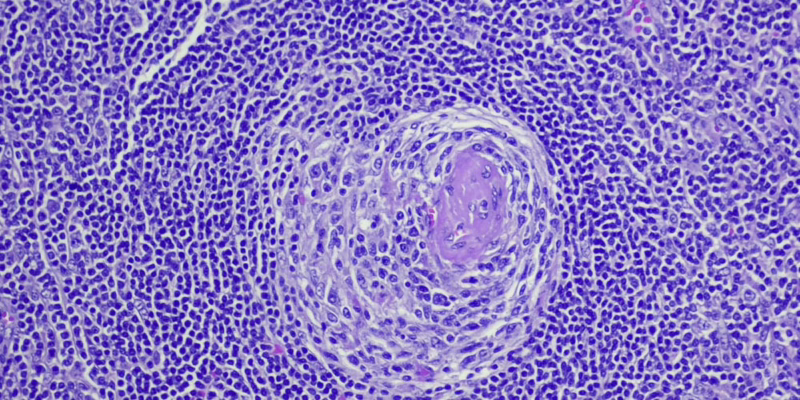

Хвороба Каслмана (ХК), вперше описана в 1956 році доктором Бенджаміном Каслманом, охоплює спектр станів, що характеризуються аномальним ростом лімфатичних вузлів і рядом симптомів від легких до таких, що загрожують життю. Історично склалося так, що ХК поділяли на НМК, що охоплює один ділянку лімфатичного вузла з більш легкими симптомами, та ІМКД, що характеризується поширеною лімфаденопатією та важким запаленням, спричиненим цитокінами. Однак досвід деяких пацієнтів із ХК не відповідає цим двом типам, що ускладнює діагностику та лікування.